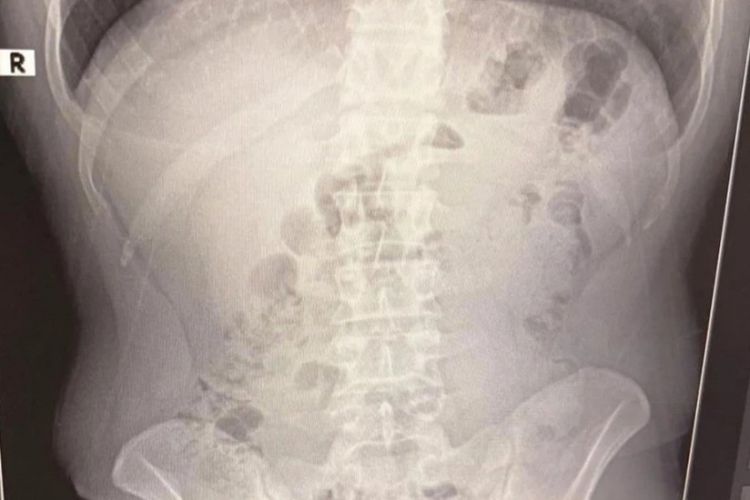

Şübhəlilər xəstəxanaya aparılıb. Rentgen müayinələrində onların mədəsində kapsul içində gizlədilmiş metamfetamin aşkar edilib. İran vətəndaşları barəsində məhkəmə həbs qətimkan tədbiri seçib.